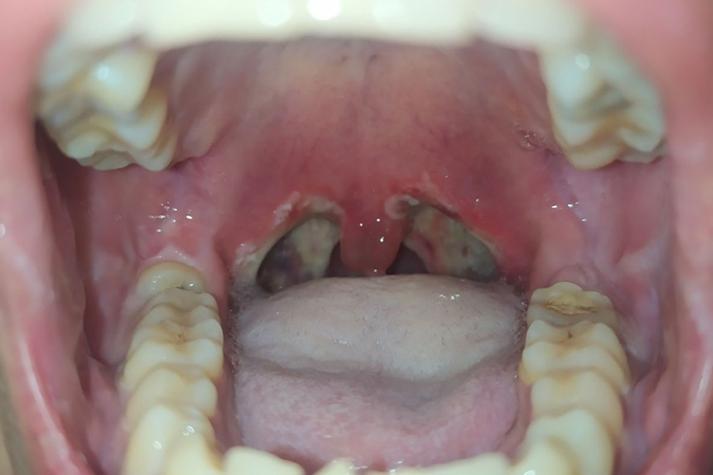

口腔念珠菌病 (Oral Thrush / 鹅口疮)

这是最常见的原因之一,由真菌(白色念珠菌)过度生长引起。

- 外观: 看起来像一层白色、奶油状、豆腐渣样的薄膜或斑块。

- 位置: 可以出现在口腔任何有粘膜的地方,包括腮帮内侧、上颚、舌头、牙龈等。

- 关键特征:

- 不易擦除: 这层膜很“顽固”,用棉签或牙刷轻轻擦拭时,它不容易被擦掉。

- 擦掉后基底: 如果强行用力擦掉,会露出下方发红、糜烂、甚至有点出血的创面,并可能感到疼痛。

- 无感或有痛感: 有时没有明显感觉,有时会感到口腔灼热、疼痛或味觉改变。